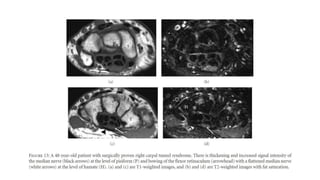

Magnetic resonance imaging (MRI) and ultrasonography :

• Measurements of the canal size.

• Flattening of the nerve at the level of hook of hamate is a usual finding.

• Cross-sectional diameter ratio of median nerve : In normal individuals it should be

one, an increase in the diameter is diagnostic. It is checked at the level of pisiform

to distal radius.

• Fatty infiltration of median nerve

• Bursitis and

• Demonstration of neuroma or other space occupying lesions.

• Incomplete resection of ligament.